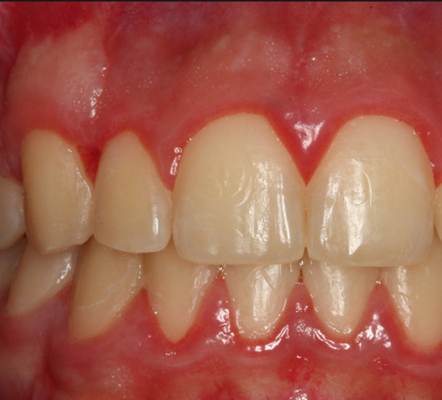

牙齦炎圖片

牙齦炎和牙周炎